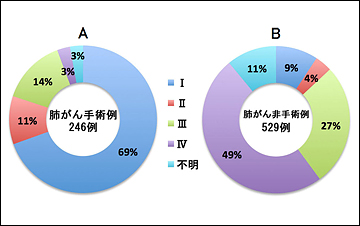

2007~2011年の5年間に当院において診療した肺がん患者の総数は775名(男性524名、女性251名、平均年齢70.8歳)でした(図1)。検査の結果から全患者の約34%が早期肺がんでしたが、残りの66%は進行肺がんと診断されました(図2)。775名中246名(全体の32%)が手術療法(外科的切除術)を受けました。手術を受けた患者のうち41名(手術患者の17%)は再発予防の抗がん剤投与による追加治療を受けました。残りの529名(68%)は、抗がん剤治療、放射線治療、緩和治療を単独または組み合わせて治療を行いました。手術療法を受けた患者と受けなかった患者の病期内訳を、それぞれ(図3)のA、Bに示しました。

図3 当院肺がん症例における手術の有無別の病期内訳(2007~2011年)